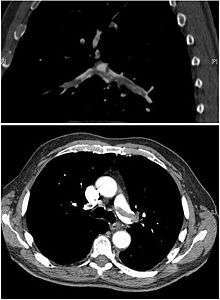

(A) After inhalation of 20 mCi of Xenon-133 gas, scintigraphic images were obtained in the posterior projection, showing uniform ventilation to lungs.

(B) After intravenous injection of 4 mCi of Technetium-99m-labeled albumin, scintigraphic images shown here in the posterior projection. This and other views showed decreased activity in multiple regions.

A ventilation/perfusion scan (or V/Q scan or lung scintigraphy) shows that some areas of the lung are being ventilated but not perfused with blood (due to obstruction by a clot).[16] This type of examination is as accurate as multislice CT, but is less used, due to the greater availability of CT technology. It is particularly useful in people who have an allergy to iodinated contrast, impaired renal function, or are pregnant (due to its lower radiation exposure as compared to CT).[49][50] The test can be performed with planar two-dimensional imaging, or single photon emission tomography (SPECT) which enables three-dimensional imaging.[43] Hybrid devices combining SPECT and CT (SPECT/CT) further enable anatomic characterization of any abnormality.